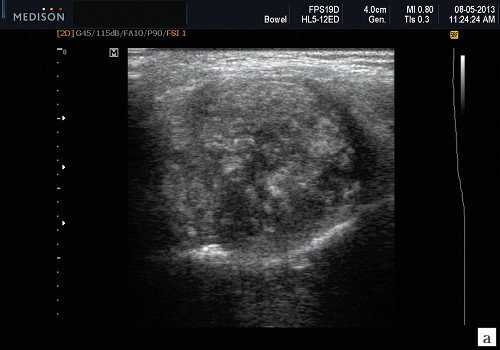

Результаты ультразвукового исследования слюнной железы

- Серошкальное УЗИ. Одиночное солидное образование в паренхиме околоушной или подчелюстной железы. Может иметь хорошо выраженные, дольчатые или плохо очерченные / инфильтративные границы. Гипоэхогенная структура по отношению к паренхиме слюнной железы. Общее улучшение ультразвукового изображения задних структур. Иногда центральный кистозный компонент представляет некроз. Могут наблюдаться связанные аномальные интрапаротидные, перипаротидные, шейные лимфатические узлы

- Цветной допплер. Внутриузловая васкуляризация от умеренной до выраженной

Результаты КТ. Солидное образование мягких тканей слюнной железы. Повышенное напряжение по сравнению с околоушной и подчелюстной паренхимой. Изоаттенуация по сравнению с мышцами. При КТ с контрастированием однородное или неоднородное усиление ± внутренний некроз

- Доброкачественная смешанная опухоль (плеоморфная аденома). Хорошо выраженная, дольчатая, однородная опухоль. На УЗИ заднее акустическое усиление. Редкая васкуляризация

- Опухоль Вартина. Четко выраженное гипоэхогенное внутрижелезистое образование. Гетерогенная внутренняя архитектура с солидным и кистозным компонентами. Обычно располагается в околоушной части хвоста. У 20% пациентов на УЗИ имеет мультицентрический характер

- Мукоэпидермоидная карцинома. Хорошо / плохо выраженный, однородный / неоднородный край в зависимости от степени злокачественности опухоли. Выраженная васкуляризация ± инфильтрация соседних тканей, метастатические лимфатические узлы

- Аденоидно-кистозная карцинома. Плохо / четко выраженные, однородные / неоднороднык края в зависимости от степени злокачественности опухоли. Выраженная васкуляризация. Склонность к периневральной инфильтрации